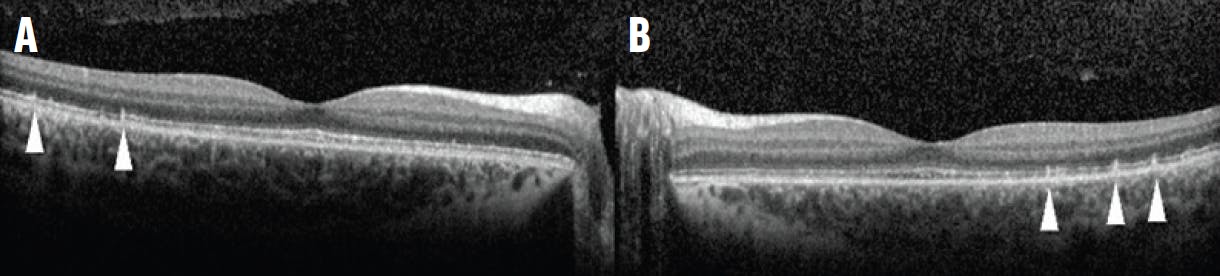

An 11-year-old boy with a history of microcephaly and developmental delay was referred for retinal screening. His VA was 20/40 in each eye. Fundus examination and widefield fluorescein angiography (FA) demonstrated avascular peripheral retina and geographic chorioretinal atrophy in the inferior midperiphery of each eye (Figure 1). OCT showed well-preserved inner and outer retina laminations in the central macula, but the outer retina became attenuated leading up to the inferior area of atrophy (Figure 2).

Figure 2. Spectral-domain OCT of the right (A) and left (B) eyes shows that overall microanatomy of the macula is intact, except for the start of outer retinal attenuation approaching the area of atrophy inferiorly.